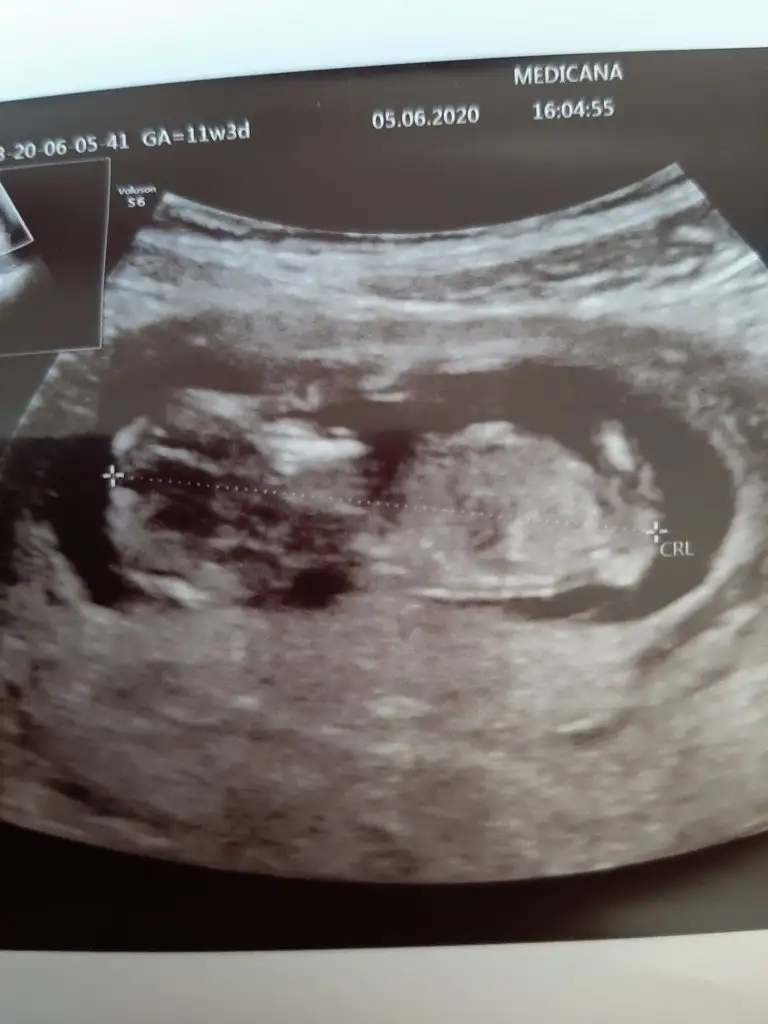

Saglıkla gelsin minnoşIkra meyra 11. Hafta ultrason görüntüme erkek demiştin. Bugün öğrendim, erkek.

Nubu ne dik nede paralel 11 yada 12 hafta usg varsa paylaşın emin olamadım çünki nubu tam karşıya bakıyorMerhaba 13+2 deyim. Cinsiyetini öğrenemedim. Yorumlarsanız sevinirim.

usg 12 hafta ile uyumlu bana da bakar mısın rica etsem canmAynen daha iyi ise usg net tahmin edilir

Kız gibi geldi emin olamadım 13 haftayıda paylaşınusg 12 hafta ile uyumlu bana da bakar mısın rica etsem canm